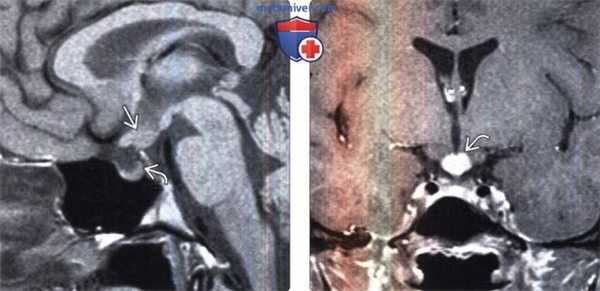

(Слева) МРТ, Т1-ВИ, сагиттальный срез: у семилетней девочки с центральным несахарным диабетом в структуре гипоталамуса визуализируется мягкотканное объемное образование. Обратите внимание на отсутствие нормального очага укорочения Т1 в гипофизе (задней доли), что часто обнаруживается у детей с несахарным диабетом.

(Справа) МРТ, постконтрастное Т1-ВИ, режим подавления сигнала от жира, корональный срез: у этого же ребенка отмечается контрастное усиление узлового образования гипоталамуса. Утолщение стебля гипофиза является наиболее частым признаком вовлечения в процесс ЦНС при гистиоцитозе из клеток Лангерганса (ГКЛ)..